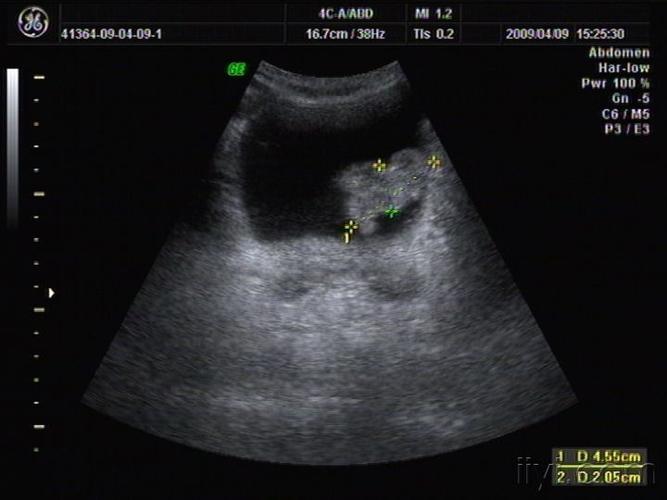

典型膀胱占位两例!(膀胱癌)

膀胱占位